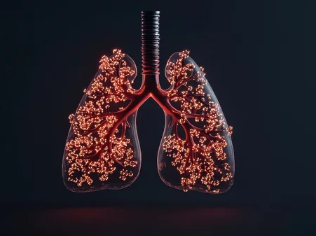

간질성 폐질환(Interstitial Lung Disease, ILD)은 **폐 조직(간질, Interstitium)**에 염증과 섬유화가 생겨 폐 기능이 점점 저하되는 질환입니다.

간질성 폐질환은 폐포(공기가 드나드는 작은 공기 주머니)와 폐혈관을 둘러싼 조직(간질, Interstitium)에 염증이 생기고 점차 섬유화(Fibrosis)로 진행되는 질환입니다.

- 폐 조직이 딱딱해지고(섬유화) 폐가 산소 교환을 원활하게 하지 못함